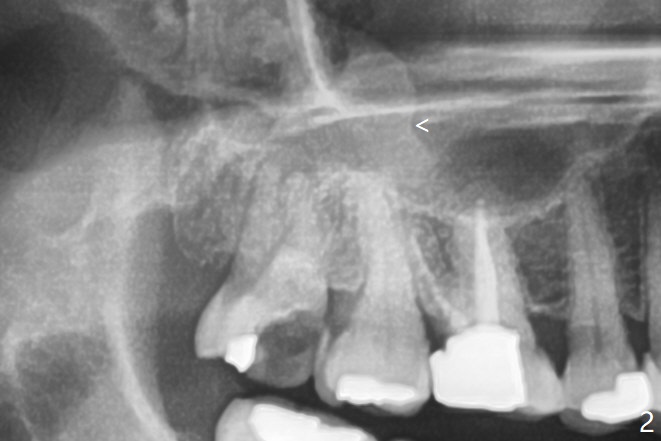

智齿与上颌窦囊肿       Last     Next